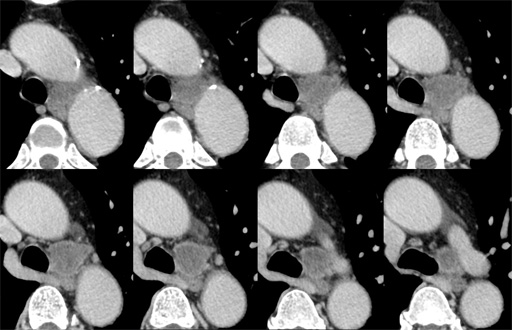

(thinsection) 図5 胸部CT 縦隔条件

図5 胸部CT 縦隔条件

(sagittal image) 図6 胸部CT 肺野条件